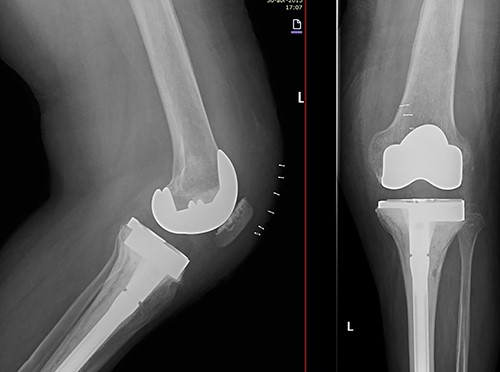

Due to the poor bone quality and defect associated to osteonecrosis (Fig. 3), osteosynthesis was discarded and total knee arthroplasty (TKA) was performed with lateral tibial block and diaphyseal stem (Fig. 4). Microbiological samples confirmed the absence of infection. Pathological samples confirmed osteolysis and chronic synovitis with osteoporosis and osteonecrosis, leading to the pathological fracture (Figs 5 and 6).

X-ray of the left knee showing reconstruction with 10-mm tibial lateral block and a tibial diaphyseal stem.

In the early postoperative period, no complications were detected, with pain decrease. After 4 years, the patient’s active ROM was 0–110° bilaterally, with no signs of radiological loosening (Fig. 9) and no pain, leading an unrestricted walking daily life without aids.

Both knees standing radiographs at 4-year follow-up with no signs of radiological loosening.